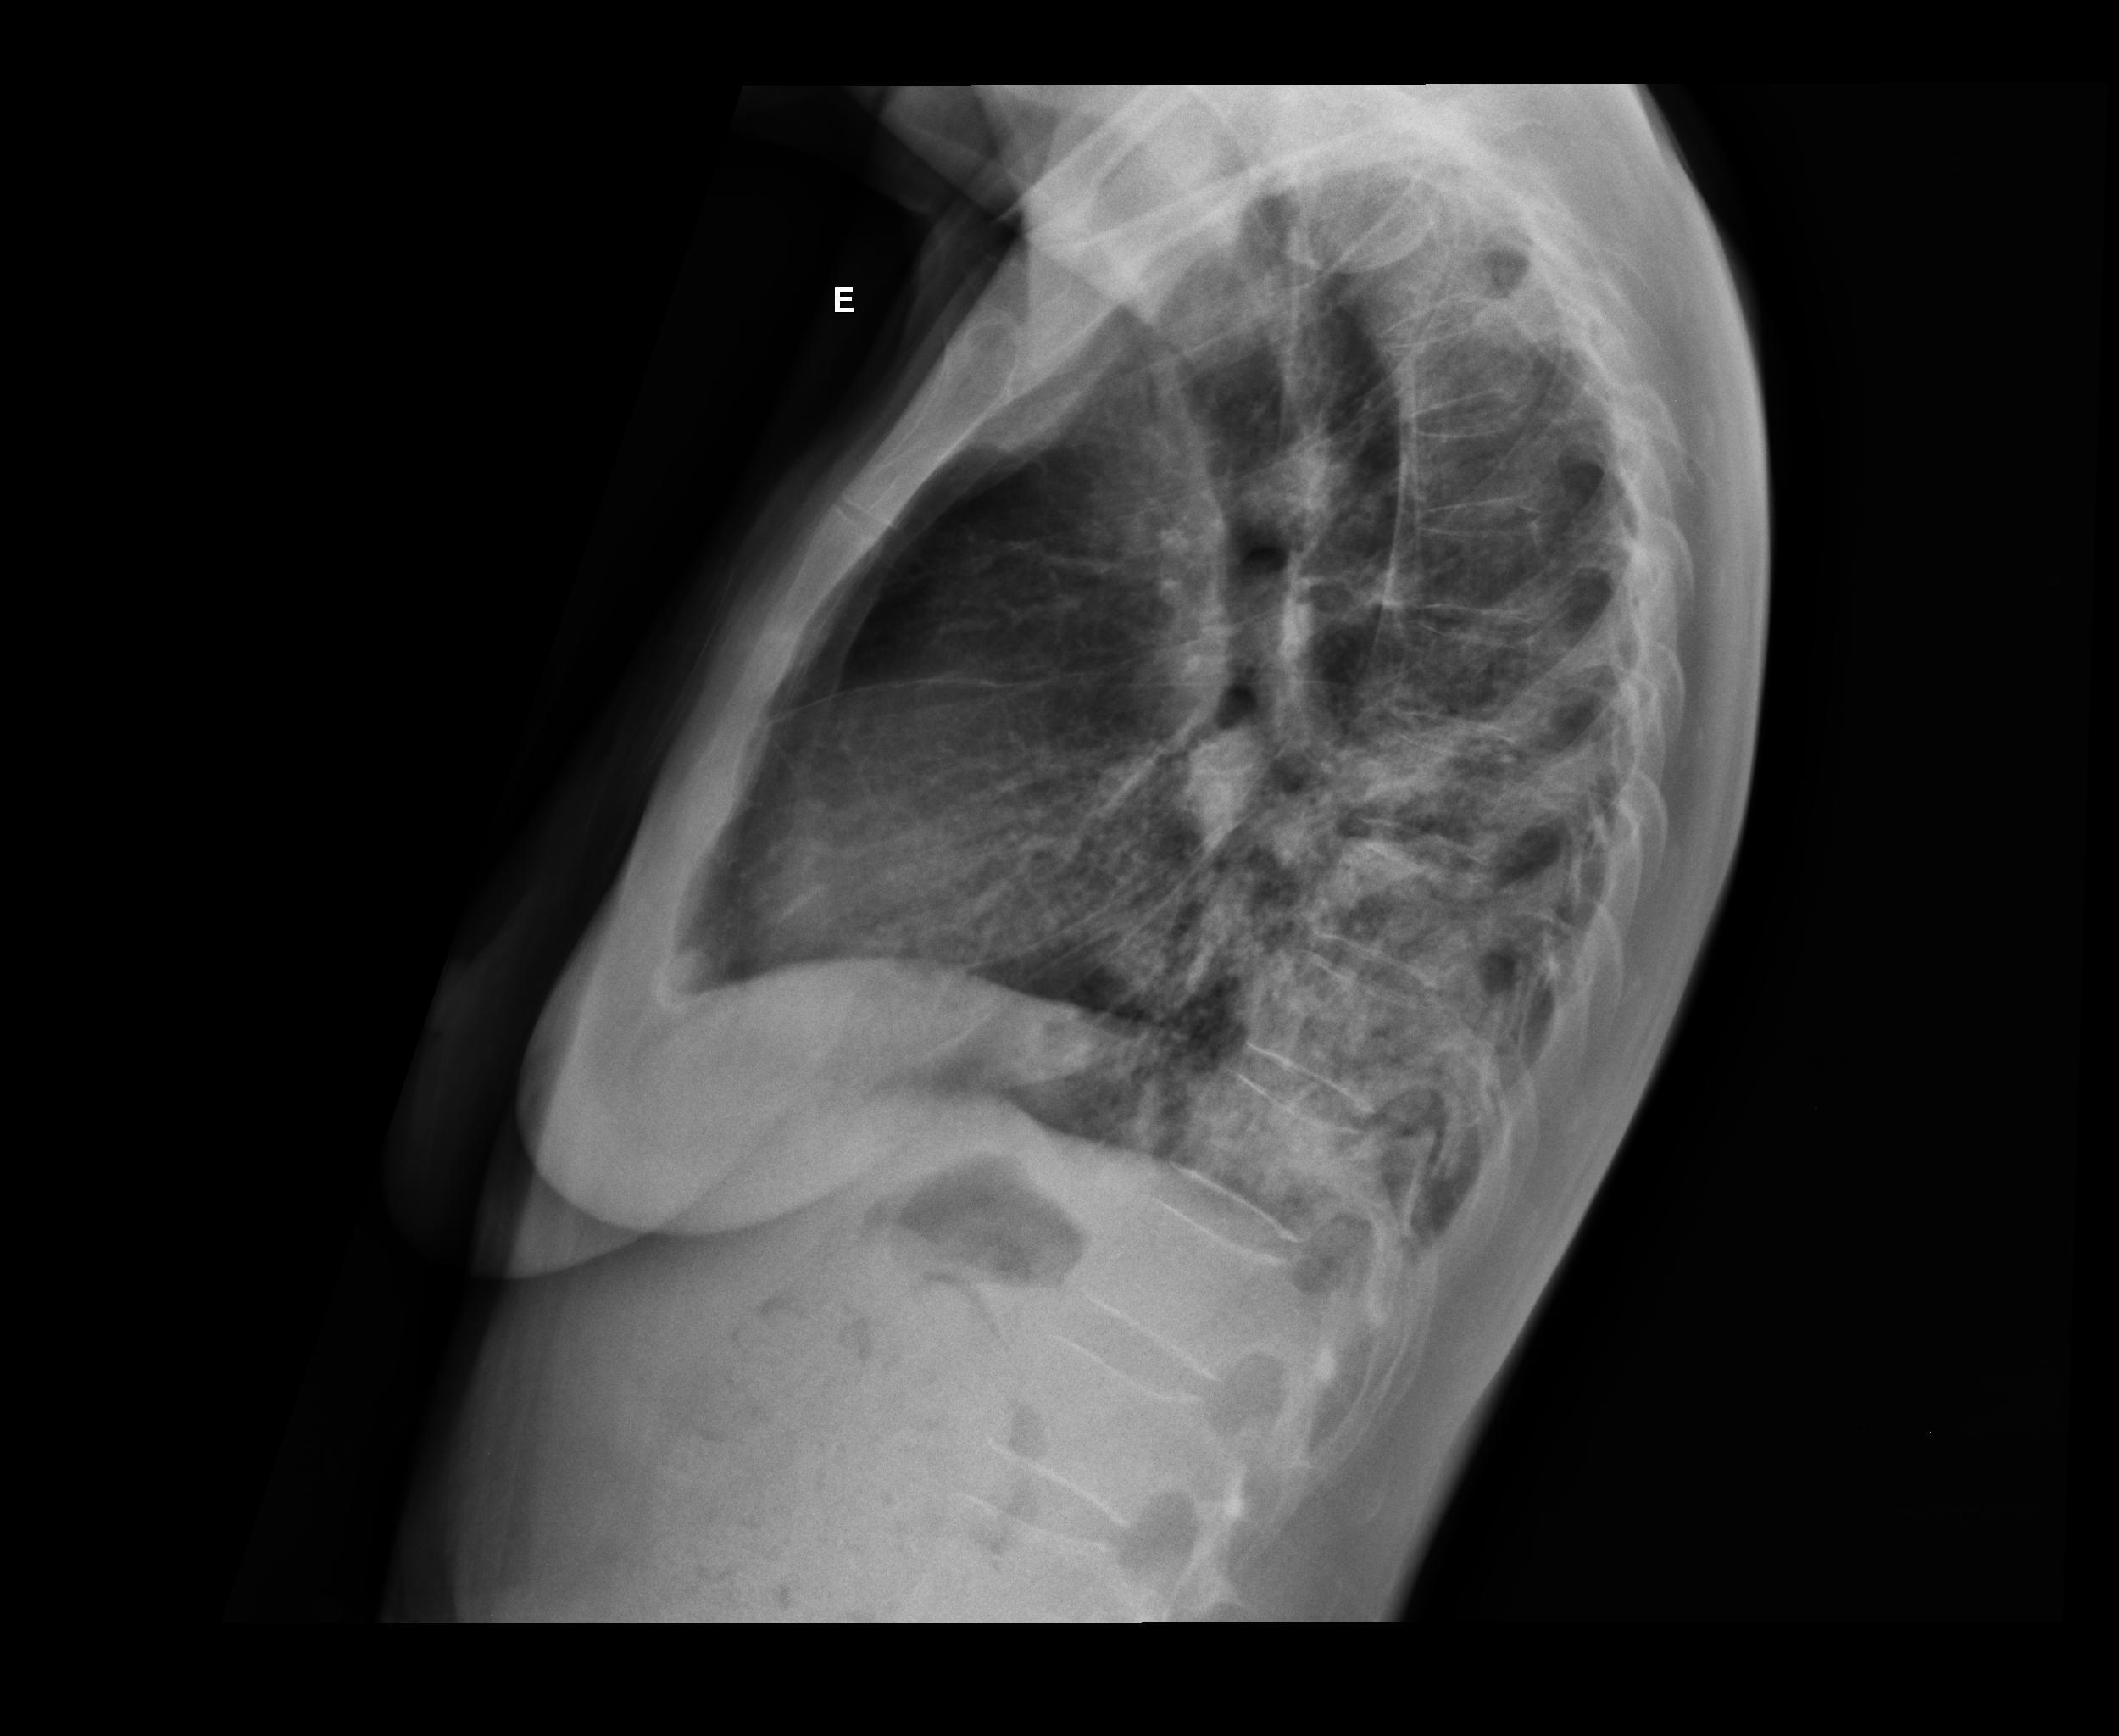

Caso relatado na Reunião de Discussão de Casos Clínicos do Hospital Universitário Prof. Polydoro Ernani de São Thiago, iniciada pelos Profs. Jorge Dias de Matos, Marisa Helena César Coral e Rosemeri Maurici da Silva, em julho de 2017. No dia 14 de junho de 2018, no auditório do HUPEST, realizou-se a apresentação e discussão do caso cujo registro é apresentado a seguir. Trata-se da discussão de onze casos em radiologia torácia, de forma interativa com a plateia, e assim ocorre também neste artigo.